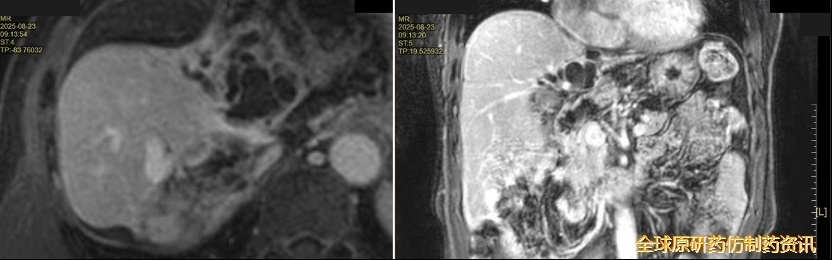

维持治疗3年后复查(2025.08)

上腹部CT(2025.08.23):肝左叶及右叶S6、7段多发异常信号影,拟治疗后改变。

图15 CT复查结果